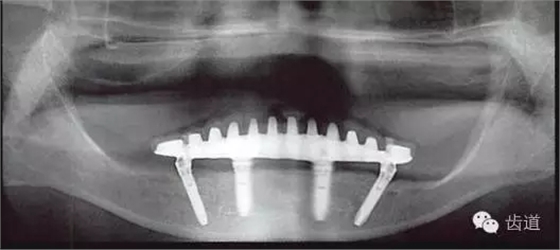

本例種植修復(fù)的問(wèn)題

咬合平面前高后低

與上頜弓有垂直向?qū)ξ魂P(guān)系的,僅有雙側(cè)第一磨牙